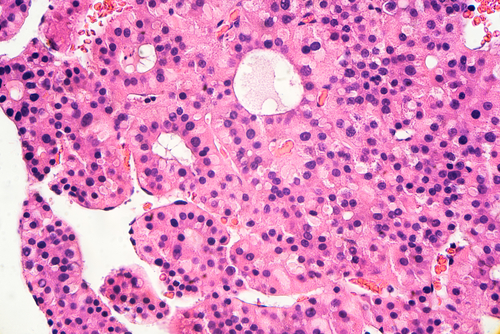

An exploratory analysis of findings from the phase III REFLECT trial suggests that an objective response could serve as a surrogate endpoint for prolonged overall survival (OS) in patients with hepatocellular carcinoma (HCC).

Masatoshi Kudo, MD, PhD, of the Kindai University Faculty of Medicine in Japan, and fellow REFLECT investigators used the data from this large, global, randomized trial, which was designed to establish the noninferiority of first-line lenvatinib versus sorafenib in 954 patients with unresectable HCC, to analyze the correlation between objective response and OS irrespective of treatment.